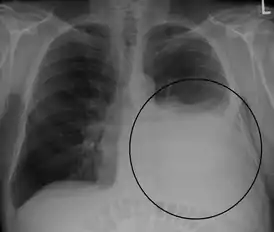

Рентгенологическое исследование позволяет обнаружить гомогенную тень жидкости с верхней границей, смещающейся при наклоне тела. Обязательным условием правильного распознавания плеврального выпота является рентгенологическое исследование в латеропозиции. С помощью ультразвукового метода можно выявить даже небольшое количество жидкости в плевральной полости и выбрать место для плевральной пункции.